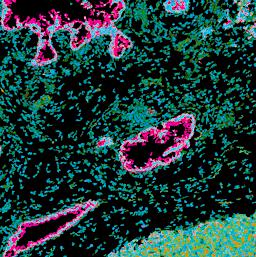

Pancreatic ductal adenocarcinoma is a lethal disease with limited treatment options and poor survival. We studied 83 spatial samples from 31 patients (11 treatment-naïve and 20 treated) using single-cell/nucleus RNA sequencing, bulk-proteogenomics, spatial transcriptomics and cellular imaging. Subpopulations of tumor cells exhibited signatures of proliferation, KRAS signaling, cell stress and epithelial-to-mesenchymal transition. Mapping mutations and copy number events distinguished tumor populations from normal and transitional cells, including acinar-to-ductal metaplasia and pancreatic intraepithelial neoplasia. Pathology-assisted deconvolution of spatial transcriptomic data identified tumor and transitional subpopulations with distinct histological features. We showed coordinated expression of TIGIT in exhausted and regulatory T cells and Nectin in tumor cells. Chemo-resistant samples contain a threefold enrichment of inflammatory cancer-associated fibroblasts that upregulate metallothioneins. Our study reveals a deeper understanding of the intricate substructure of pancreatic ductal adenocarcinoma tumors that could help improve therapy for patients with this disease.